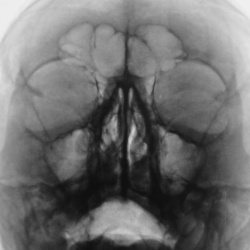

Мужчина, лет 55, неделю назад "упал", было носовое кровотечение и припухлость в обл. левой скулы. Коллеги, сколько переломов ?